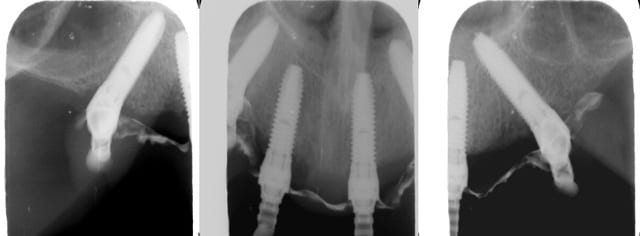

Ginette j60 qhdbxm - Eugenol

Rx pnlu5j - Eugenol

J'oubliais... douleurs 0, bien etre 100%, proprioception en cours, aucun devissage spontané, serrage 15 newton.

j' ai juste retravaillé très ponctuellement le contact muqueux sous la selle (en distal de la 22) pour compenser une perte legere de contact consécutive à la fin de l' oedeme muqueux... bref, ça faisait un peu zozotter ginette qui méritait pas ça ;)